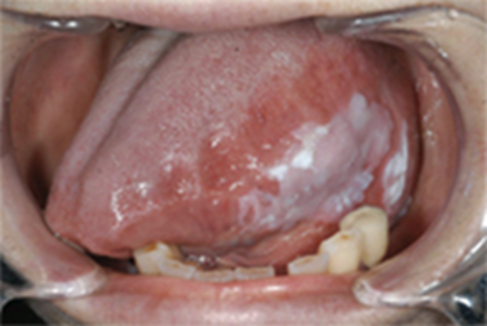

こんにちは。鳴門市の和田歯科医院の歯科医師の中原です。 口腔粘膜疾患とは口腔粘膜疾患とは口の中の粘膜(舌、歯肉、口蓋、頬など)が、白色や赤色に変色したり、水ぶくれができたり、表面の凸凹、不整な形、ヒリヒリした痛みがあるなど様々な兆候を示します。一時的なもので自然に治るものもありますが、中には癌などに変化するものもあり、注意が必要です。 主な疾患口腔粘膜疾患には、以下のようなものがあります。 アフタ性口内炎 一般的に口内炎と言われるものです。口腔内の粘膜にできる小さな潰瘍で、表面は灰白色~黄白色の偽膜で覆われ、周囲は赤くなっています。食べ物や歯ブラシなどがちょっと触れただけもズキッとした強い痛みを覚えます。アフタ性口内炎は何もしなくても1~2週間で治ります。 ![]() 原因は不明で、機械的刺激、遺伝性、極端な疲労、ストレス、あるいは偏った栄養摂取などいろいろな要素が絡み合って発症するといわれます。 白板症(はくばんしょう) 頬粘膜や舌、ときには歯肉にみられる白い病変で、こすっても剥がれないものをいいます。白板症は比較的頻度も高く、とくに舌にできたものは悪性化する可能性が高いため、口腔潜在的悪性疾患(癌に移行していく可能性があるもの)の代表的なものとされています。びらん(粘膜の浅い欠損)をともなうこともあり、ものが当たると痛かったり、食べ物がしみたりします。 ![]() 原因は喫煙やアルコールによる刺激、義歯などによる慢性の機械的刺激、ビタミンAやBの不足、さらに加齢や体質なども関係するといわれています。しこりや潰瘍をともなうものは初期癌が疑われるため、必ず組織をとって検査する必要があります。白い部分が厚いもの、隆起したもの、びらんや潰瘍を伴うものは悪性化(癌化)する可能性が高いので、切除します。長年かかって悪性化する場合もあり、長期にわたる経過観察が必要です。 カンジダ症 おもにカンジダ・アルビカンスという真菌(カビ)によっておこる口腔感染症です。口腔粘膜の痛みや味覚障害が出ることもあります。乳白色の苔のようなものが粘膜表面に付着します。この白苔をガーゼなどでぬぐうことが可能ですが、その後の粘膜面は発赤やびらんを呈しています。中には白苔が認められないものもあり、舌や粘膜が赤くなりヒリヒリとした痛みが出ることがあります。 ![]() カンジダ菌は口腔内の常在菌の一種で、普段はある程度以上は菌数が増えないように他の菌と共存しています。しかし、副腎皮質ステロイド薬の投与や糖尿病などによって免疫力が低下している状態、唾液量の減少、長期間にわたる抗菌薬の服用などにより、常在菌のバランスが崩れカンジダ菌が異常に増殖し、病原性を発揮することにより発症します。治療法は、口腔内の清掃、うがい薬や塗り薬を使用しますが、時に抗真菌薬の内服を必要とすることもあります。 扁平苔癬(へんぺいたいせん) 皮膚や粘膜にできる炎症をともなう難治性の病変です。口腔では頬粘膜に多く認めますが、舌や口唇にも生じます。粘膜表面が白くレース状にみられ、周囲に発赤を伴うのが特徴です。接触痛や、食べ物がしみたりします。まれに癌化することもあります。 ![]() 正確な原因は不明で、アレルギー、とくに歯科用金属によるものや遺伝的素因、自己免疫疾患、ストレスなどの精神的因子、さらに代謝障害などの関与が考えられています。治療にはうがい薬や軟膏を使います。歯科用金属によるアレルギーが疑われる場合は、原因と思われる詰め物や被せ物を除去する必要があります。これらを除去する前に、歯科用の金属アレルギー検査を行います。 2週間以上治らないようなら…口の中の粘膜にできる病気の代表的なものを挙げましたが、この中には「口腔潜在的悪性疾患」と呼ばれる癌化する可能性があるものもあります。普通の口内炎や硬いものが当たってできた傷なら1~2週間で治ることが多いので、2週間以上治らないような病変がある時には一度歯科医院で見てもらうことが重要です。 ![]() 当院は日本口腔外科学会の専門医が在籍しております当院は日本口腔外科学会の専門医も在籍しており、口腔粘膜疾患の診断に長けています。 診療のご予約はこちら≫ネット予約 歯科医師 中原 参考文献:日本口腔外科学会ホームページ |